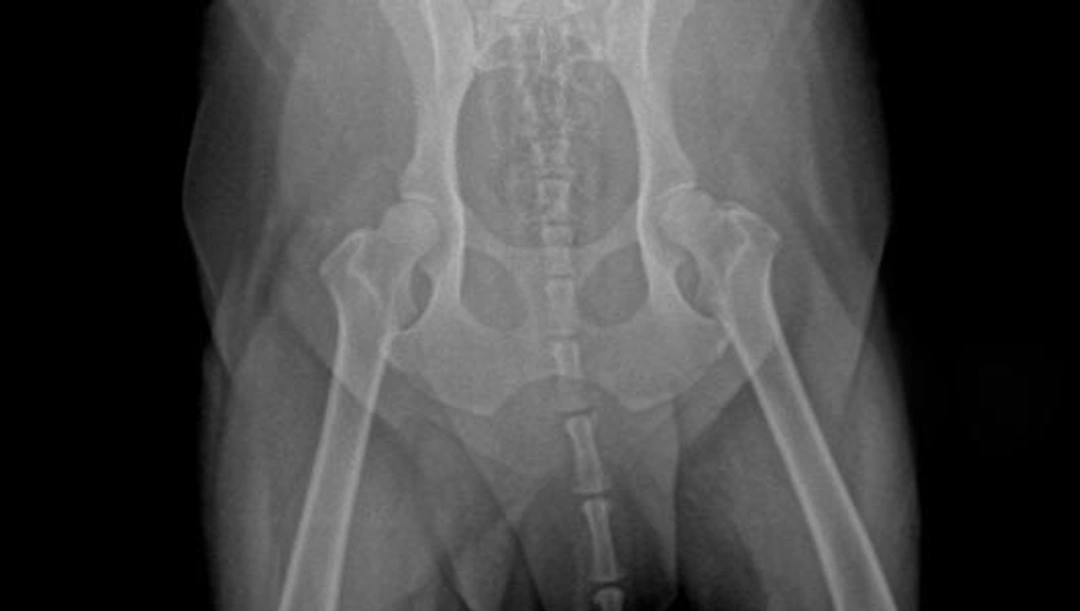

Heupdysplasie bij de hond is een multifactorieel erfelijke aandoening die onder meer bij de Duitse herder voorkomt, waarbij spontaan letsels rond de heupkop (caput femoris) en het heupgewricht (acetabulum) ontstaan. Bij mensen komt ook heupdysplasie voor.

Honden met heupdysplasie kunnen manken. In het verloop van de ziekte kan naderhand een spieratrofie ontstaan. Ook crepitatie in het gewricht kan worden gehoord of gevoeld. Naargelang de ernst van de dysplasie kan een luxatie van het heupgewricht ontstaan

Er bestaat geen medicijn waarmee heupdysplasie te genezen is. Wel zijn er behandelingen (conservatieve en/of chirurgische behandeling) en medicijnen waarmee verergering wordt voorkomen of pijnklachten worden verminderd. De conservatieve behandeling (= niet operatief) is bruikbaar bij honden met milde symptomen of bij honden die voor het eerst symptomen van kreupelheid vertonen. De behandeling kan bestaan uit aangepaste beweging (rust of juist training), aangepaste voeding en eventueel ontstekingsremmers. Het doel van een chirurgische behandeling kan de vermindering van pijn zijn, de terugkeer naar een zo normaal mogelijk gebruik van het aangetaste gewrichten het voorkomen van artrose en verdere spieratrofie. Er zijn meerdere operatietechnieken mogelijk.

1. Het kantelen van de heupkom over de heupkop. De heupkom wordt op meerdere plaatsen doorgezaagd, gekanteld totdat de heupkop goed in de heupkom past, en weer vastgezet met metalen schroeven. Hierdoor ontstaat er een betere aansluiting. Deze operatie wordt uitgevoerd bij jonge honden (ouder dan 8 maanden) met losse heupen zonder vormverandering.

2. Het weghalen van een spier in de lies. Hiermee wordt bij veranderde heupgewrichten voorkomen dat de kop in de kom wordt getrokken. Deze operatie wordt uitgevoerd bij honden waarbij deze spier is aangespannen en die misvormde heupen hebben.

3. Het weghalen van de heupkop. Dit gebeurt meestal niet bij grote honden omdat herstel niet zo goed is als bij kleine, lichtere honden.

4. Het plaatsen van een kunstheup. Dit gebeurt veelal bij honden met zeer pijnlijke heupgewrichten die ernstig misvormd zijn. Of een operatie dan wel een conservatieve behandeling voor een hond het beste is, moet beoordeeld worden door een ervaren of gespecialiseerde orthopedische dierenarts.